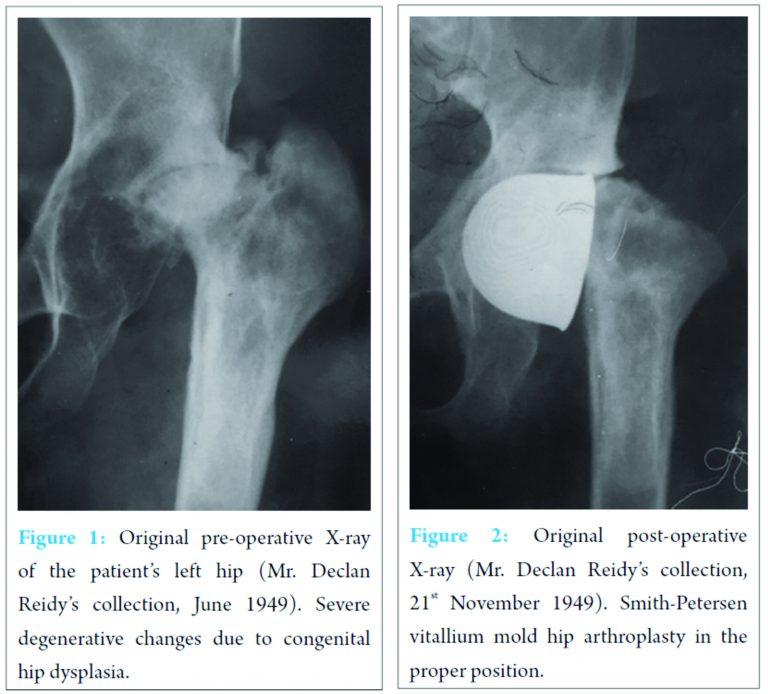

E. H. was born in 1919 with congenital dysplasia of her left hip. She had had multiple operations on it, but she still developed gross degenerative changes by the age of 30 (Fig. 1). Mr. W. Alexander Law, an orthopedic surgeon, performed a Smith-Petersen vitallium mold hip arthroplasty in October 1949 in London Hospital (Fig. 2).